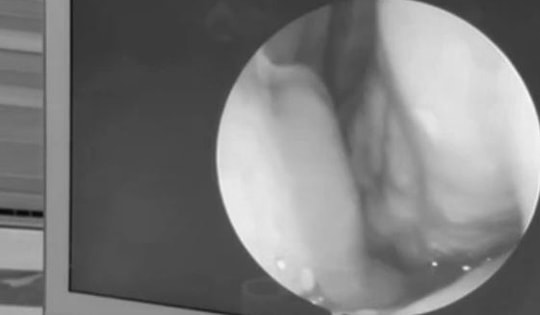

Thấy trẻ bị đau tai kèm chảy máu, gia đình đưa đi khám thì sốc nặng

Trước khi nhập viện khoảng 4 ngày, bệnh nhi thường xuyên có biểu hiện ngoáy tai sau đó xuất hiện tình trạng đau tai tăng dần, kèm theo máu chảy ở tai trái nên gia đình đã đưa trẻ đi khám.